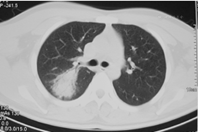

21例患者均行肺电子计算机断层扫描(CT)检查,提示双肺单发(2例)或多发(19例)的斑片状、条片状、团片状、结节状、磨玻璃样高密度影,边界模糊,其中2例病灶中出现含气支气管影。单个病灶直径1~5 cm,可为单肺(9例,其中5例为右肺,4例为左肺)或双肺(12例)受累,在肺叶、段分布上无明显特异性(图1、图2、图3)。

本组病例中,患者年龄主要集中在20~40岁,既往健康情况良好,大部分患者表示既往有麻疹疫苗接种史,但均不能提供末次麻疹疫苗接种时间。患者病程自限,热程均在一周以内,平均热程为(4.5±1.7)d,1例患者仅发热半天。患者发热多在出疹后3 d内迅速退热,状态良好,除肺炎外,其他并发症相对较少且轻,仅1例患者有一过性轻微腹泻,5例患者肝功能轻度异常。患者白细胞计数正常或偏低,提示为病毒性感染。肺炎为本研究中所有患者的主要临床表现,影像学上突出表现为单发或多发的团、片状高密度影,在肺叶、段的分布上无特异性,病灶直径1~5 cm。国内对聚集性流行的不典型麻疹研究发现,成人的肺炎检出率为19.5%~54.9%(经X线检查诊断)[5,6,7],如进行肺部CT检查,则肺炎的检出率则升至31.2%~94.1%[5,7];散发的成人麻疹(包括典型麻疹病例)中肺炎检出率为6.1%~24.1%(经X线检查诊断)[8,9]。国外报道成人麻疹中,肺炎发生率为34%[10]。然而,上述研究显示,不典型成人麻疹患者尽管并发肺炎的概率较高,单个病灶范围可以较大,但咳嗽、胸痛、呼吸困难等症状不重,且病变吸收较快,患者通常一般状态佳,病程自限、预后良好[5,10],本研究结果与之相似。